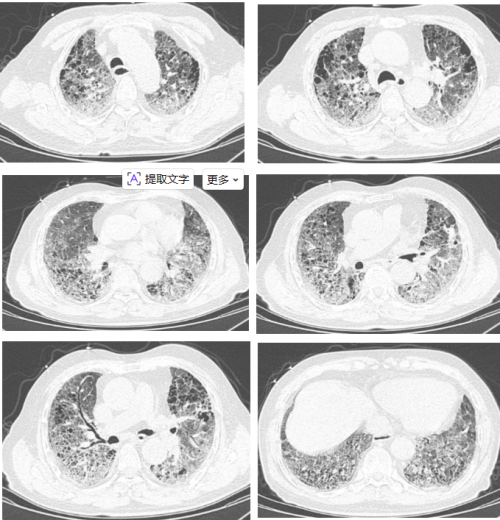

第一次入院胸部CT:

第二次入院胸部CT: